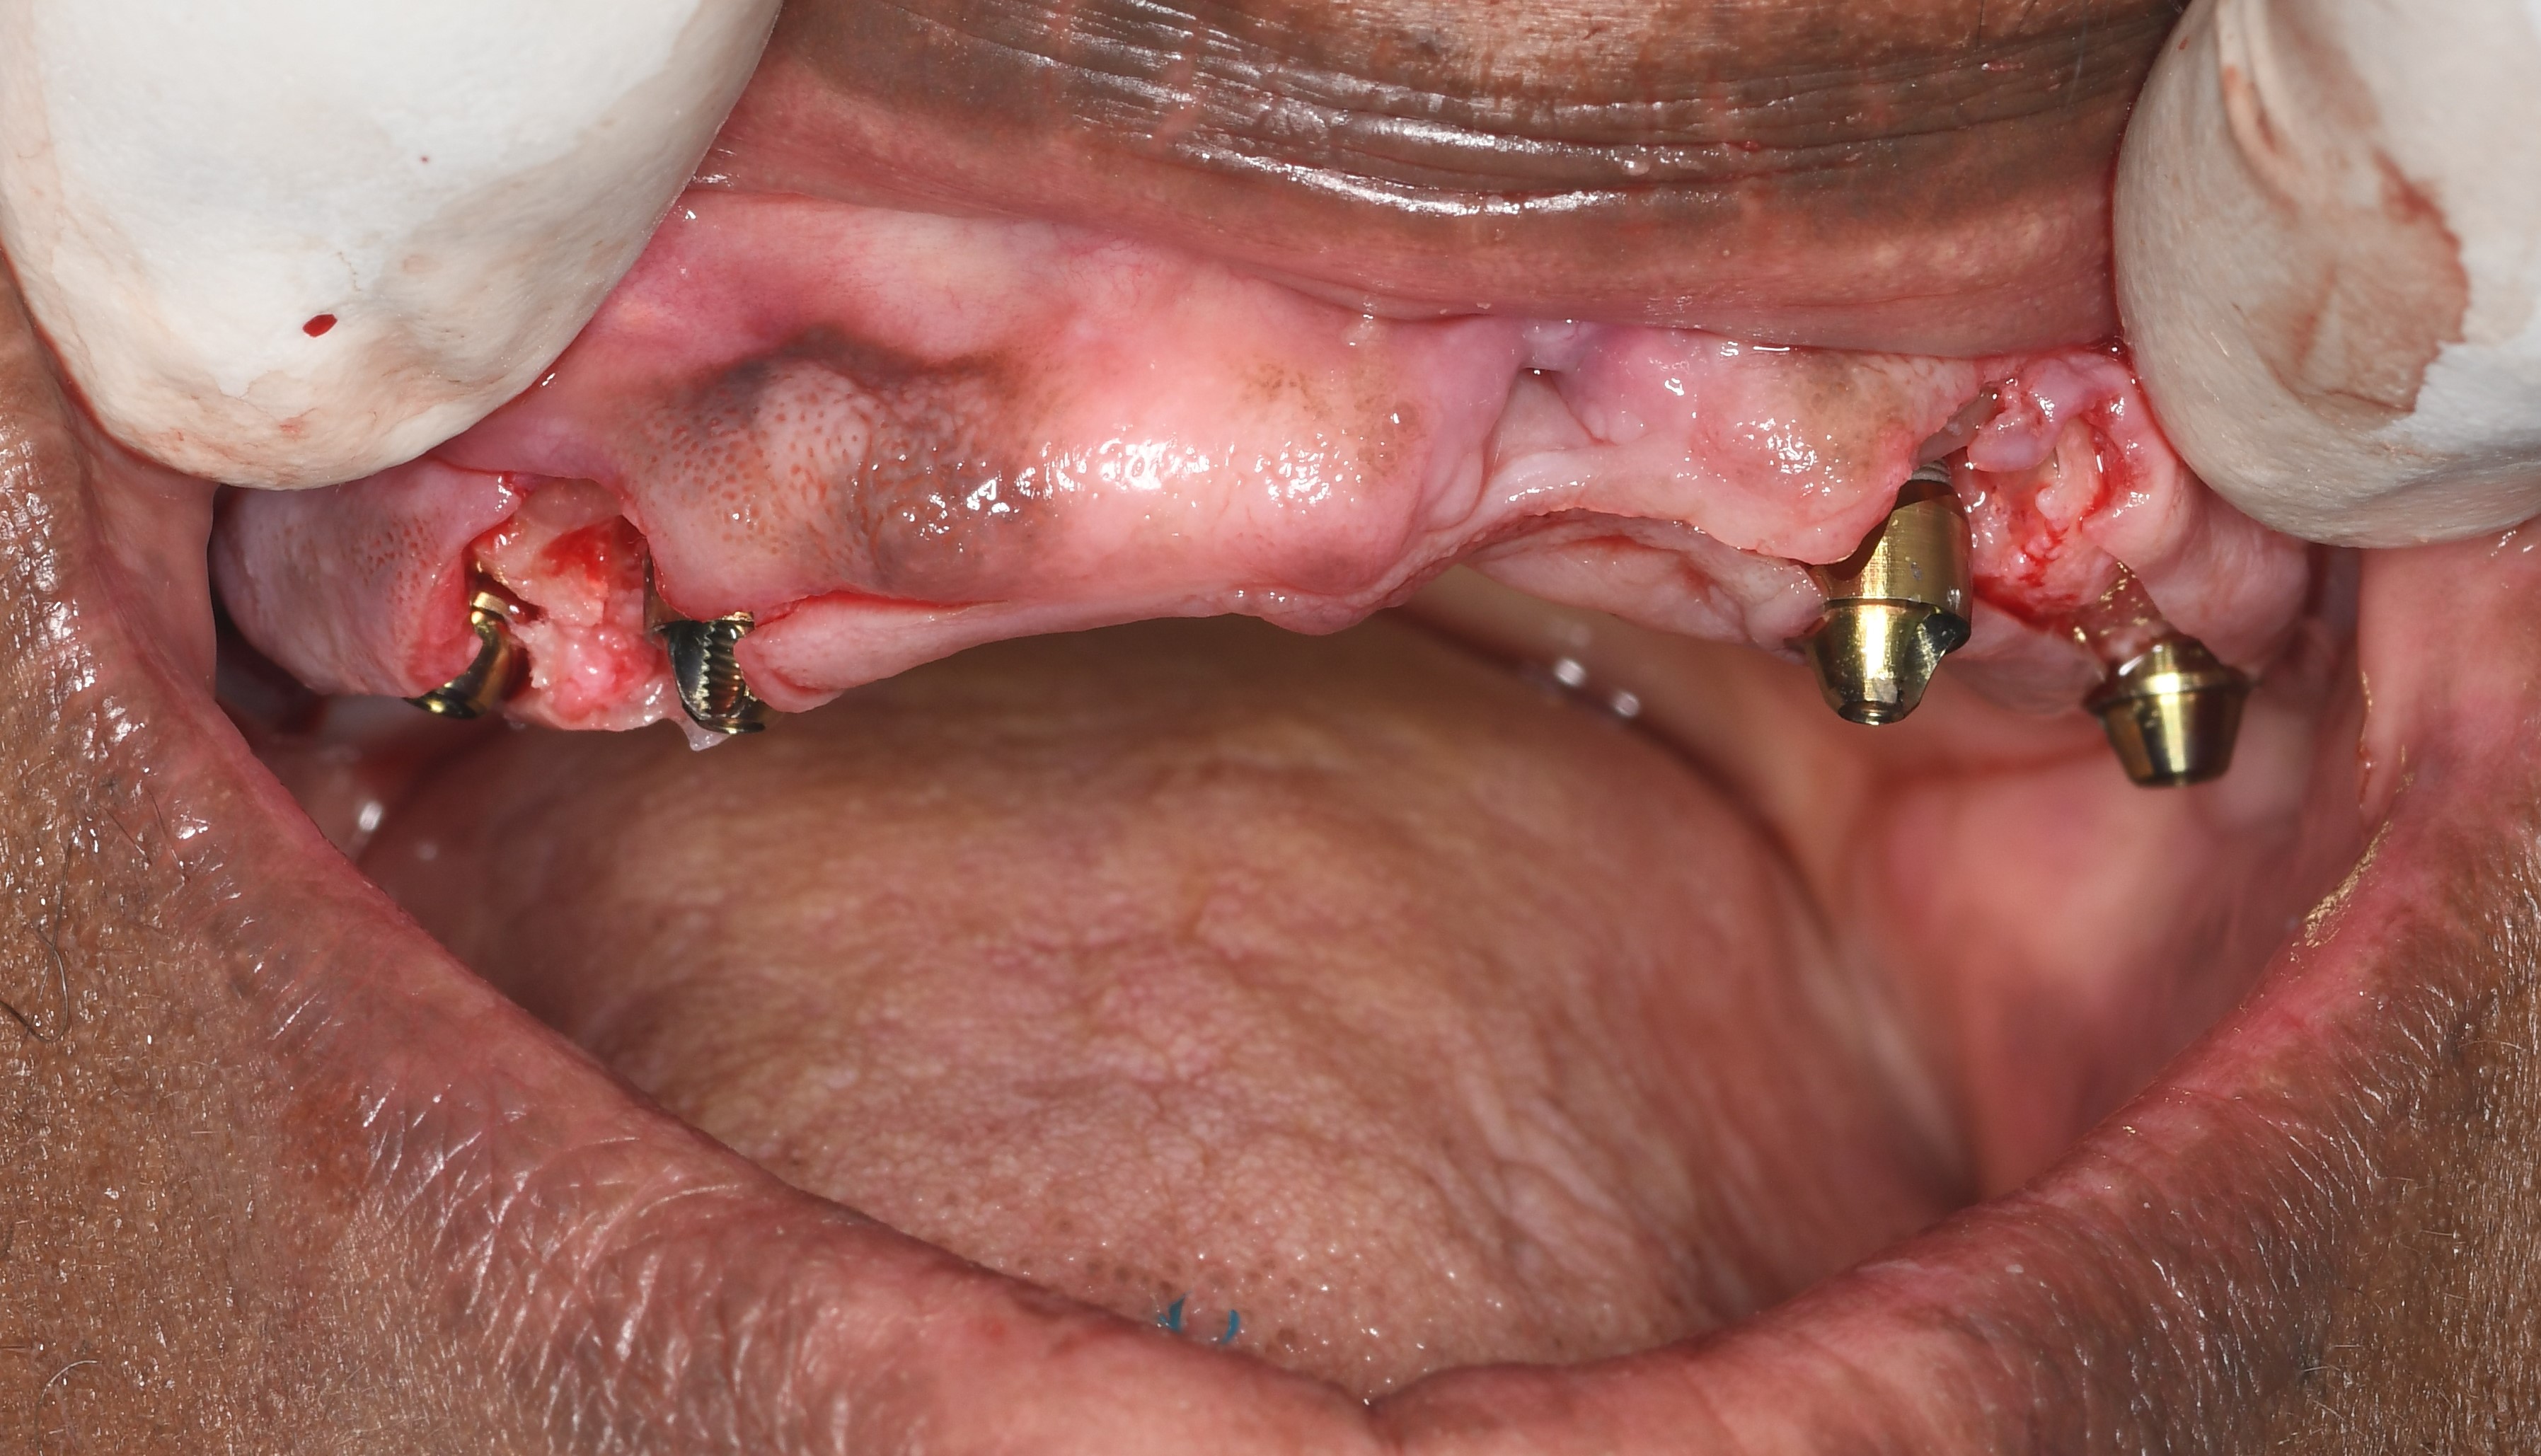

All-on-5 Multi Unit Full Mouth on Diabetic Patient

Senior patient who’s health was deteriorating because of poor eating habits. Has a history of diabetes which is controlled. So poor eating made him lose weight and would occasionally interfere with his ability to treat his diabetes condition. Had a long term denture but didn’t want it because of poor stability and poor fit.